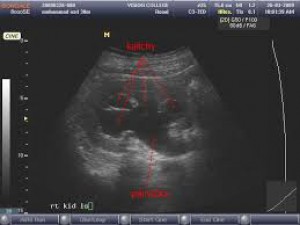

USG obličiek hlavne u nemočiacich pacientov je základné nenáročné vyšetrenie. Veľmi jednoducho kedykoľvek realizovateľné aj priamo na oddelení, napríklad INT - respektíve všade tam, kde je USG prístroj k dispozícii.

Stačí priložiť sondu na lumbálnu oblasť a odlíšiť fyziologický prierez obličky od hydronefrotického - čo nemôže byť problém. Okamžite zistíte či potrebujete nefrológa, alebo urológa.